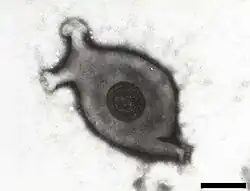

| Electron micrograph of Mycoplasma gallisepticum, scale bar 140 nm | |